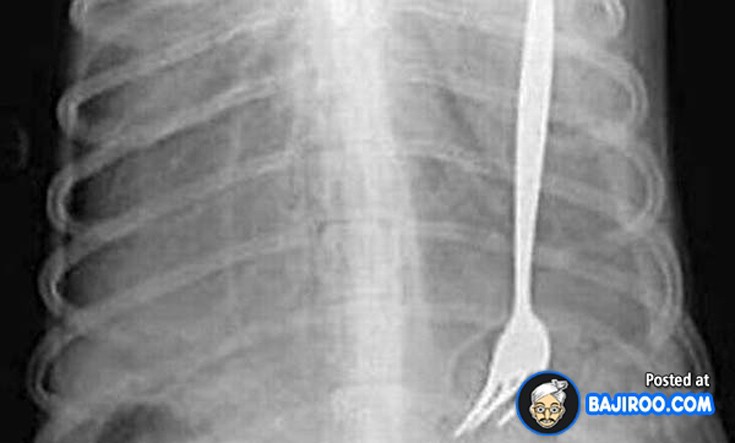

Ο,ΤΙ ΝΑ 'ΝΑΙ #ακτινογραφίες Παράξενα πράγματα που έχουν δείξει οι ακτινογραφίες Από δαχτυλίδια μέχρι πιρούνια και καρφιά - Δείτε τις φωτογραφίες 15·04·2016 11:08 1 σχόλια